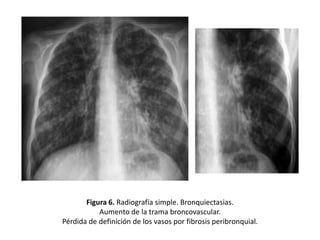

• Pérdida de definición de los vasos pulmonares

y agrupamiento de la trama broncovascular

por fibrosis peribronquial. (Figura 6)

Figura 6. Radiografía simple. Bronquiectasias.

Aumento de la trama broncovascular.

Pérdida de definición de los vasos por fibrosis peribronquial.